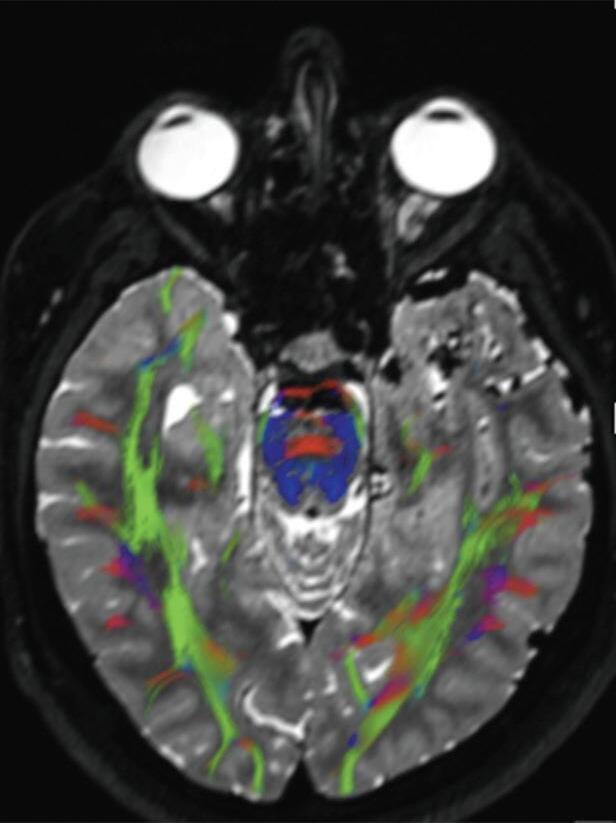

A utilização de técnicas avançadas, como a tractografia (Fig. 1-23), reconstruções 3D, permitem um estudo detalhado de estruturas anatômicas e sua relação com as patologias cerebrais, facilitando assim o planejamento cirúrgico. A tractografia, uma técnica de ressonância magnética, permite estudar os tratos da substância branca do cérebro, mostrando sua posição, anatomia e integridade, por meio da análise do movimento das moléculas de água no tecido cerebral.35

tractografia cerebral, cortes axiais. A codificação de cores demonstra as fibras com orientação laterolateral em vermelho, a orientação anteroposterior em verde e a craniocaudal em azul. Observe o deslocamento das fibras de associação (verde) no lobo temporal esquerdo em relação à MAV.